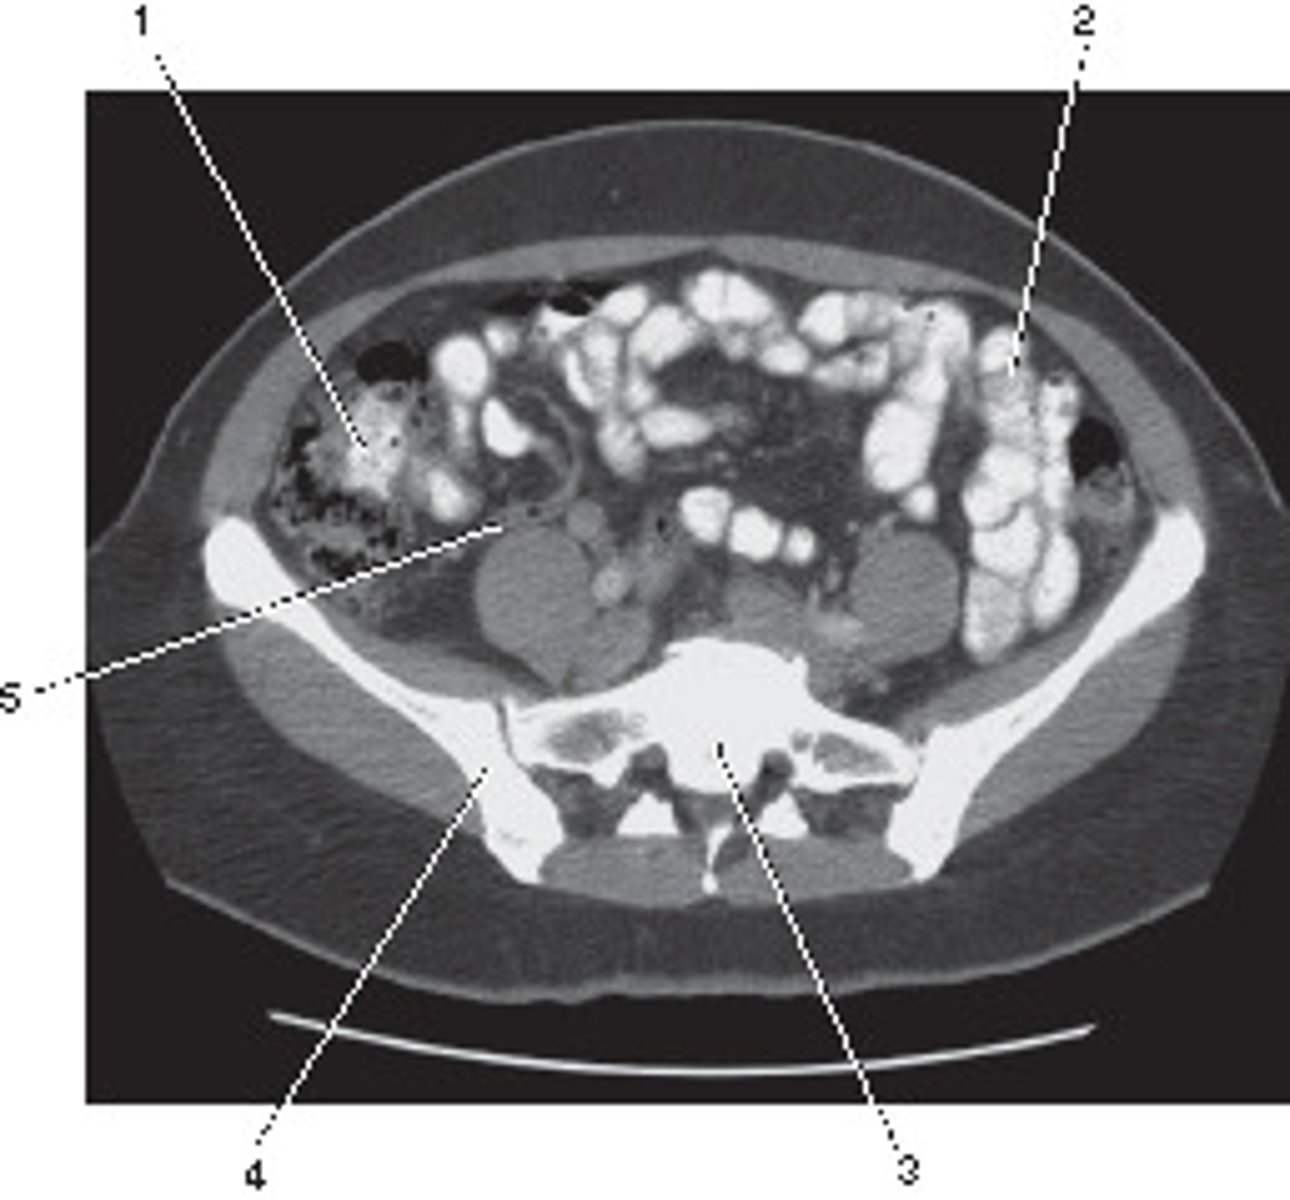

Ileum

Number 1 corresponds to which of the following?

<p>Number 1 corresponds to which of the following?</p>

Ilium

Number 4 corresponds to which of the following?

<p>Number 4 corresponds to which of the following?</p>